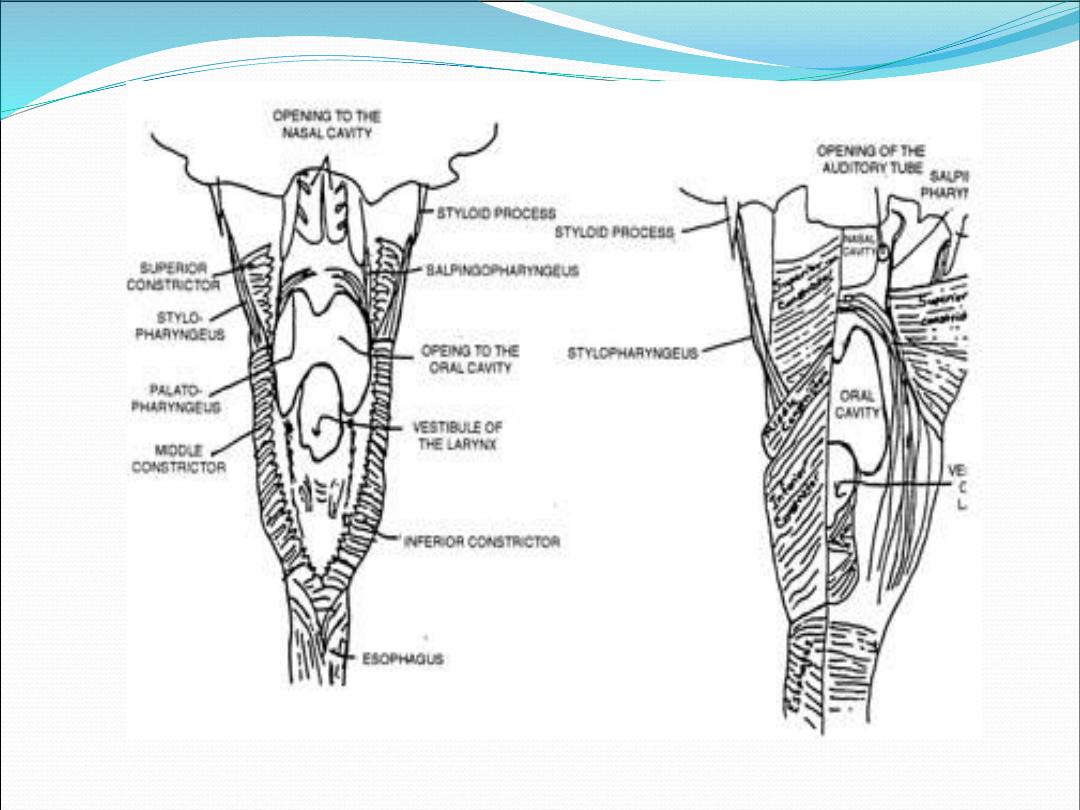

Inner layer

Salpingopharyngeus

Stylopharyngeus

Stylohyoid

Palatopharyngeus (posterior pillar)

Outer layer (constrictors)

Superior constrictor

Middle constrictor

Inferior constrictor